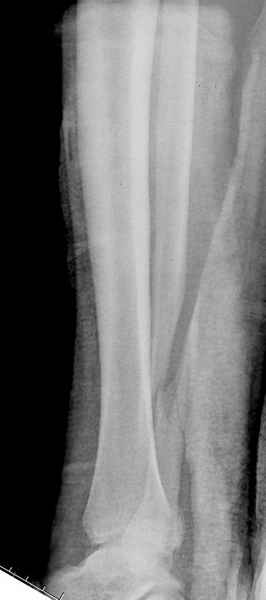

>На сделанных у нас снимках видно, что не все благополучно...

Неравномерность суставной щели может быть связана с разрывом глубокой порции дельтовидной связки и ротацией м/берцовой кости за счет поврежденных структур синдесмоза(репозиция ее на уровне перелома как-будто удовлетворительная).

Импрессия медиальной части суставной поверхности бывает при супинационном механизме перелома лодыжек (тип А по классификации АО). Здесь механизм пронациия+наружная ротация (тип С, синдесмоз и межкостная мебрана повреждены),

перелом медиальной лодыжки отрывной, при этом в 20-30% бывает повреждение дельтовидной связки.

Клиновидность щели сустава следствие повреждения дельты, невосстановления длины малоберцовой или (хотел сказать "установки в гипсе", но оного, вроде,

Мое мнение, что никакой ротации малоберцовой кости здесь нет и синдесмоз тоже впорядке. Все дело в некачественно репозиции медиального мыщелка. Скорее всего его или немного ротировали при операции или сместили латерально. Более склонен ко второму варианту.

При реконструкции голеностопа, о важности восстановления длины малоберцовой для профилактики пост травматического артроза разбирали в предыдущих дискуссиях. Нарушенную биомеханику голеностопа без восстановления длины малоберцовой, не восстановить только швом медиальной связки.

Расширенная медиальная щель более чем на 4 мм и укорочение малоберцовой более чем 2 мм, а перелом заднего края большеберцовой смещения более 2мм с вовлечением 30% поверхности сустава, считается отходом от нормы голеностопного сустава, и подлежит к оперативному вмещательству.